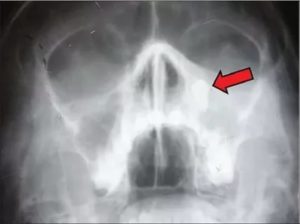

При подозрении на гайморит любой природы обязательно проводится рентгенологическое исследование. Процедура отличается неинвазивностью и доступностью. Практически в каждом медицинском учреждении можно сделать снимок носовых пазух.

Съёмку выполняют в заднебоковой, аксиальной, боковой, подбородочной и носоподбородочной проекциях. При отсутствии воспаления и новообразований полости на снимке представлены тёмными кругами неправильной формы. Если имеет место воспаление, то в полости заметны тени. Полипозный очаг выглядит как небольшое белесое пятно.